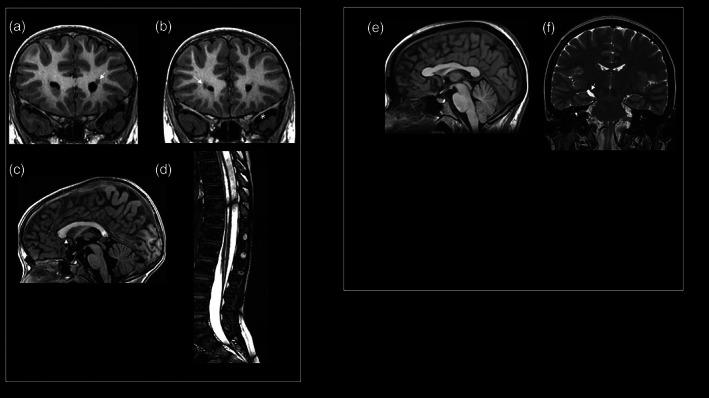

Nuclear Factor I B (NFIB) haploinsufficiency has recently been identified as a cause of intellectual disability (ID) and macrocephaly. Here we report on two new individuals carrying a microdeletion in the chromosomal region 9p23-p22.3 containing NFIB. The first is a 7-year 9-month old boy with developmental delays, ID, definite facial anomalies, and brain and spinal cord magnetic resonance imaging findings including periventricular nodular heterotopia, hypoplasia of the corpus callosum, arachnoid cyst in the left middle cranial fossa, syringomyelia in the thoracic spinal cord and distal tract of the conus medullaris, and a stretched appearance of the filum terminale. The second is a 32-year-old lady (the proband' mother) with dysmorphic features, and a history of learning disability, hypothyroidism, poor growth, left inguinal hernia, and panic attacks. Her brain magnetic resonance imaging findings include a dysmorphic corpus callosum, and a small cyst in the left choroidal fissure that marks the hippocampal head. Array-based comparative genomic hybridization identified, in both, a 232 Kb interstitial deletion at 9p23p22.3 including several exons of NFIB and no other known genes. Our two individuals add to the knowledge of this rare disorder through the addition of new brain and spinal cord MRI findings and dysmorphic features. We propose that NFIB haploinsufficiency causes a clinically recognizable malformation-ID syndrome.